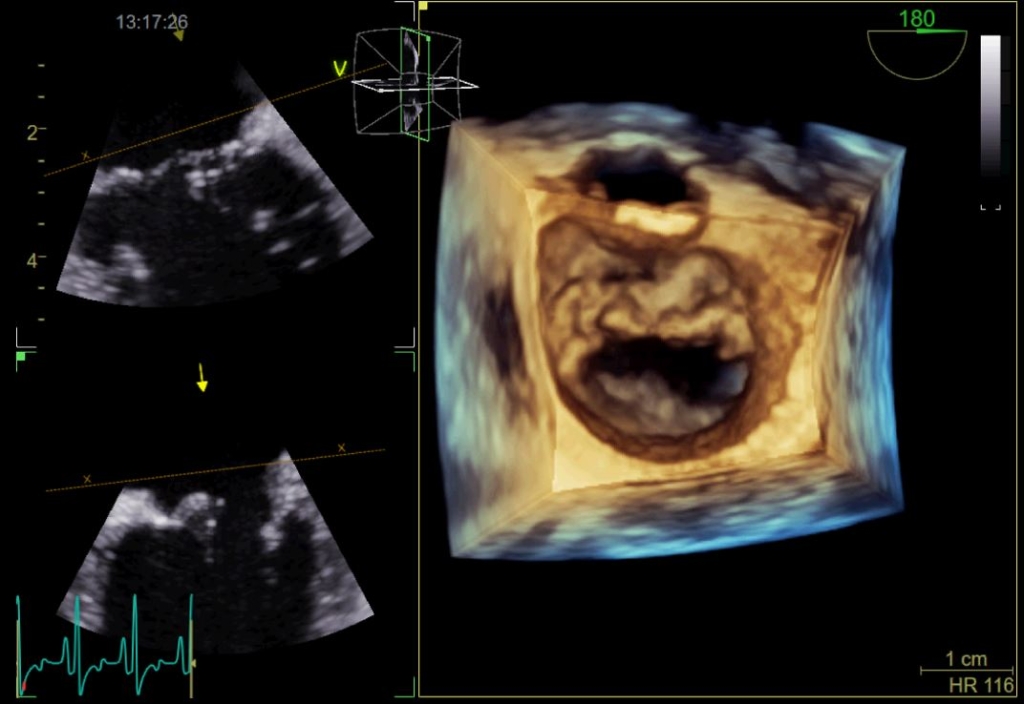

A high-resolution 3D image of a dog’s heart, captured on the new 3D transoesophageal (TOE) probe at Willows Veterinary Centre and Referral Service in Solihull, West Midlands.

Fabio said: “The 3D TOE probe is a state-of-the-art piece of equipment and technology that allows us to acquire a detailed 3D echocardiogram.

“Unlike traditional 2D echocardiograms, which provide flat, two-dimensional images, a 3D TOE generates three-dimensional, live images of the heart.

“This allows for a more comprehensive and detailed view of the heart's chambers, valves, and blood flow patterns resulting in a better visualisation of complex cardiac structures and abnormalities, making it valuable for diagnosing and assessing various heart conditions.”